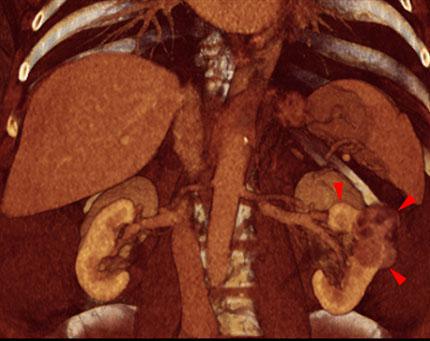

Hipernefroma 1